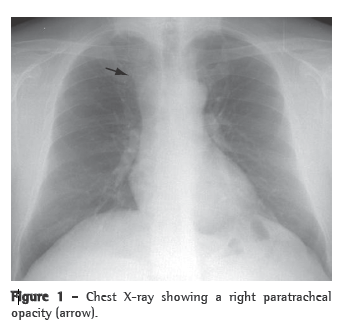

Computed tomography of the chest revealed a right paratracheal mediastinal tumor, 4.5 cm in diameter, in contact with the right tracheal wall and causing anterior deviation of the brachiocephalic vein and superior vena cava. The mass had regular borders and spontaneous low density, was homogeneous, and showed no enhancement after administration of contrast medium (Figure 2).

The presumed diagnosis is made based on the detection of a cystic lesion on a chest X-ray or a computed tomography scan of the chest.(5) On X-rays, lymphangiomas of the mediastinum appear as well-circumscribed, round masses of homogeneous density,(5) and computed tomography of the chest demonstrates the involvement or deviation of natural structures, absence of calcification, and various high attenuation areas within the lesion.(2)